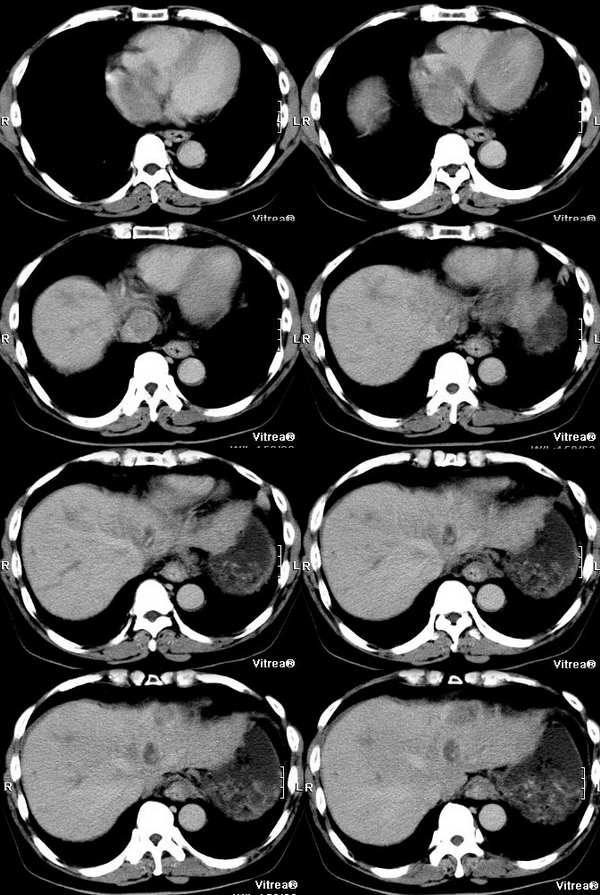

男性,58岁,肝硬化数年,近几个月出现黄疸,腹胀,食欲下降,尤其双下肢浮肿明显。超声提示肝脏多个结节。ct三期扫描图像如下:

动脉期:

门脉期:

平衡期:

动静脉期见门静脉,下腔静脉增宽,无强化,右心房有无强化的低密度影,肝左叶轻度不均匀强化,平衡期见病灶密度减低,肝内胆管扩张.肝尾叶增大.动脉期见肝左静脉明显强化并向右心房的特异性侧支循环.

肝左叶不规则肿块,血供不丰富,早期强化不明显,三期符合肝癌块尽快出的特点。门静脉、腔静脉近右房段增粗,早期见癌栓滋养血管强化明显。

肝静脉:在动脉期的第一张图片上就可以看到右心房的充盈缺损和下腔静脉近心段的明显增粗,增粗的下腔静脉内部可以见到点状、条状的强化血管影,这些强化的血管影是什么来源?这些高密度影蜿蜒曲折,和主动脉同时显影,所以只能考虑为主动脉的分支血管之一。到门脉期和平衡期,右心房的充盈缺损更加明显了,肝静脉和下腔静脉的强化非常微弱,肝段下腔静脉的管腔十分狭窄,但肝外段的下腔静脉明显的饱满,这是由于右心房的充盈缺损和下腔静脉近心段的栓子梗阻造成的。在动脉期肝左叶有一条横行血管也非常引人注目,考虑为肝左静脉的可能,但其汇入腔静脉端呈一盲端,估计终止于栓子部位,该血管的过早显影提示存在动静脉分流,从病因上来说以原发性肝癌最为常见。在临床上,该患者有双下肢明显的浮肿,要用下腔静脉的梗阻来解释。

门静脉:门静脉不论在门静脉期还是实质期(其实对于这个病人来说,我们平常所说的门静脉期还是实质期已经不适用了)均未见显影,在实质期反而发现门静脉和周围密度增高的肝实质相比呈低密度,这说明门静脉主干和主要分支均形成栓子。由于正常情况下,肝脏的大部分血供来自门静脉,这就造成了肝脏的强化幅度明显下降。在胰头勾突前方可以见到扩张的血管分支,应该为门静脉的侧枝循环血管,但是奇怪的一点是脾脏不大,不太好解释。

肝动脉:从动脉期看,肝门区肝动脉及其分支明显的增粗、增多。非常值得注意的是肝左叶见到明显扩张的肝动脉分支,这是动脉期估计肿瘤部位的重要线索。

肝实质:该患者既有门静脉供血的下降又有肝静脉的回流异常,形成了比较复杂的强化效果。由于门静脉为入肝血管,它的梗阻造成肝脏的强化幅度明显下降,但在延迟扫描时,其引流范围内的血液会经过侧枝循环逐渐进入,所以其密度会缓慢地上升。另外又由于肝静脉的回流异常,会引起布查氏综合征的密度改变,造成肝实质密度不均匀。

肿瘤:由于肝脏本身存在血液循环的异常,所以肿瘤的血供也会受到影响。该患者在动脉期肝左叶见到明显扩张的肝动脉分支和肝左静脉的早期显影,强烈提示左叶病变。尽管没有见到明显的动脉期肿瘤强化,但仔细观察还是有动脉供血病变的,不过密度较淡,边缘模糊;在平衡期,左叶肿瘤露出其真面目,和肝脏实质相比呈低密度。由于患者有多年肝硬化病史和存在动静脉分流和静脉栓子,综合考虑还是应该首先考虑为原发性肝癌。另外腔静脉内栓子动脉期明显动脉供血,也是肝癌癌栓的特征,这一点和hejie的意见不同。

肝脏超声提示多发占位,仔细观察动脉期在肝脏左右叶交界和肝右叶后段均可以见到小片状强化,尽管不很典型也应该考虑为癌瘤,由于肝脏多发的癌瘤,造成了门静脉、肝静脉系的广泛癌栓。